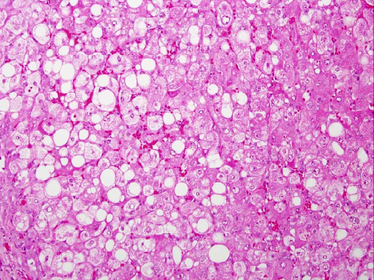

TISSUE TYPE: preserved liver PATHOLOGY: vacuoles of fatty subestance DIAGNOSIS: liver steatosis KEY: VACUOLATION

Fatty liver